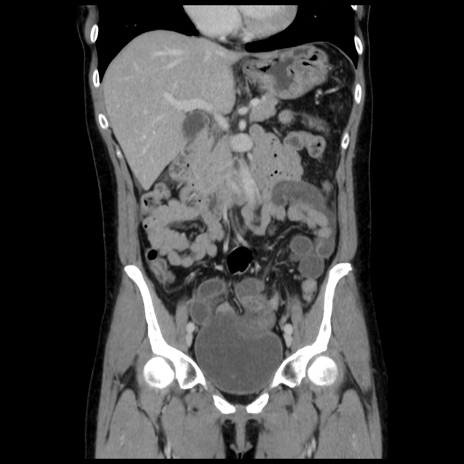

症例10(冠状断像)

【症例】 50歳代女性

【主訴】 腹痛

【現病歴】前日生レバーを食べた。今朝に排便あり。 昼前に突然発症の腹痛を生じ、当院救急外来を受診した。

【既往歴】 子宮筋腫にてで子宮全摘後

【身体所見】 意識清明、腹部:平坦、軟、下腹部やや左を中心に圧痛・反跳痛あり、筋性防御あり

【データ】WBC 7800、CRP 0.07